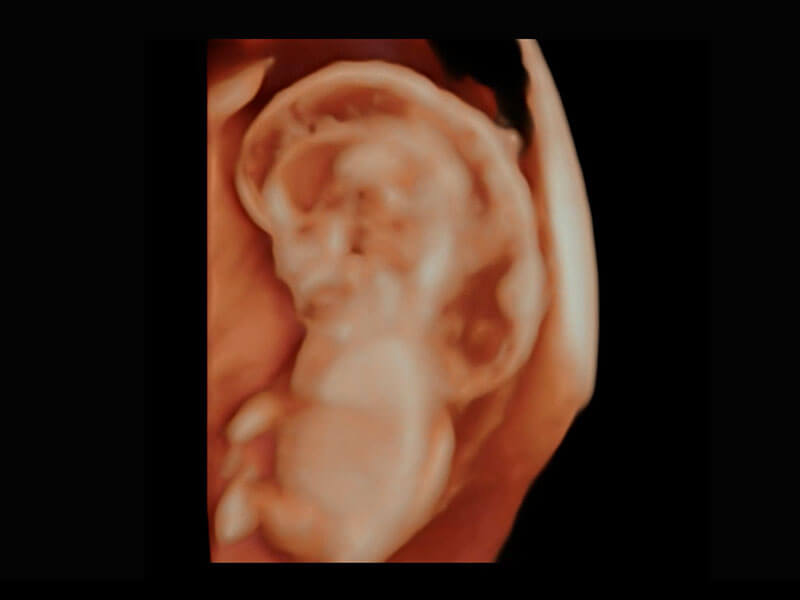

• 高分辨率容积成像-早孕胎儿

• 胎儿体循环